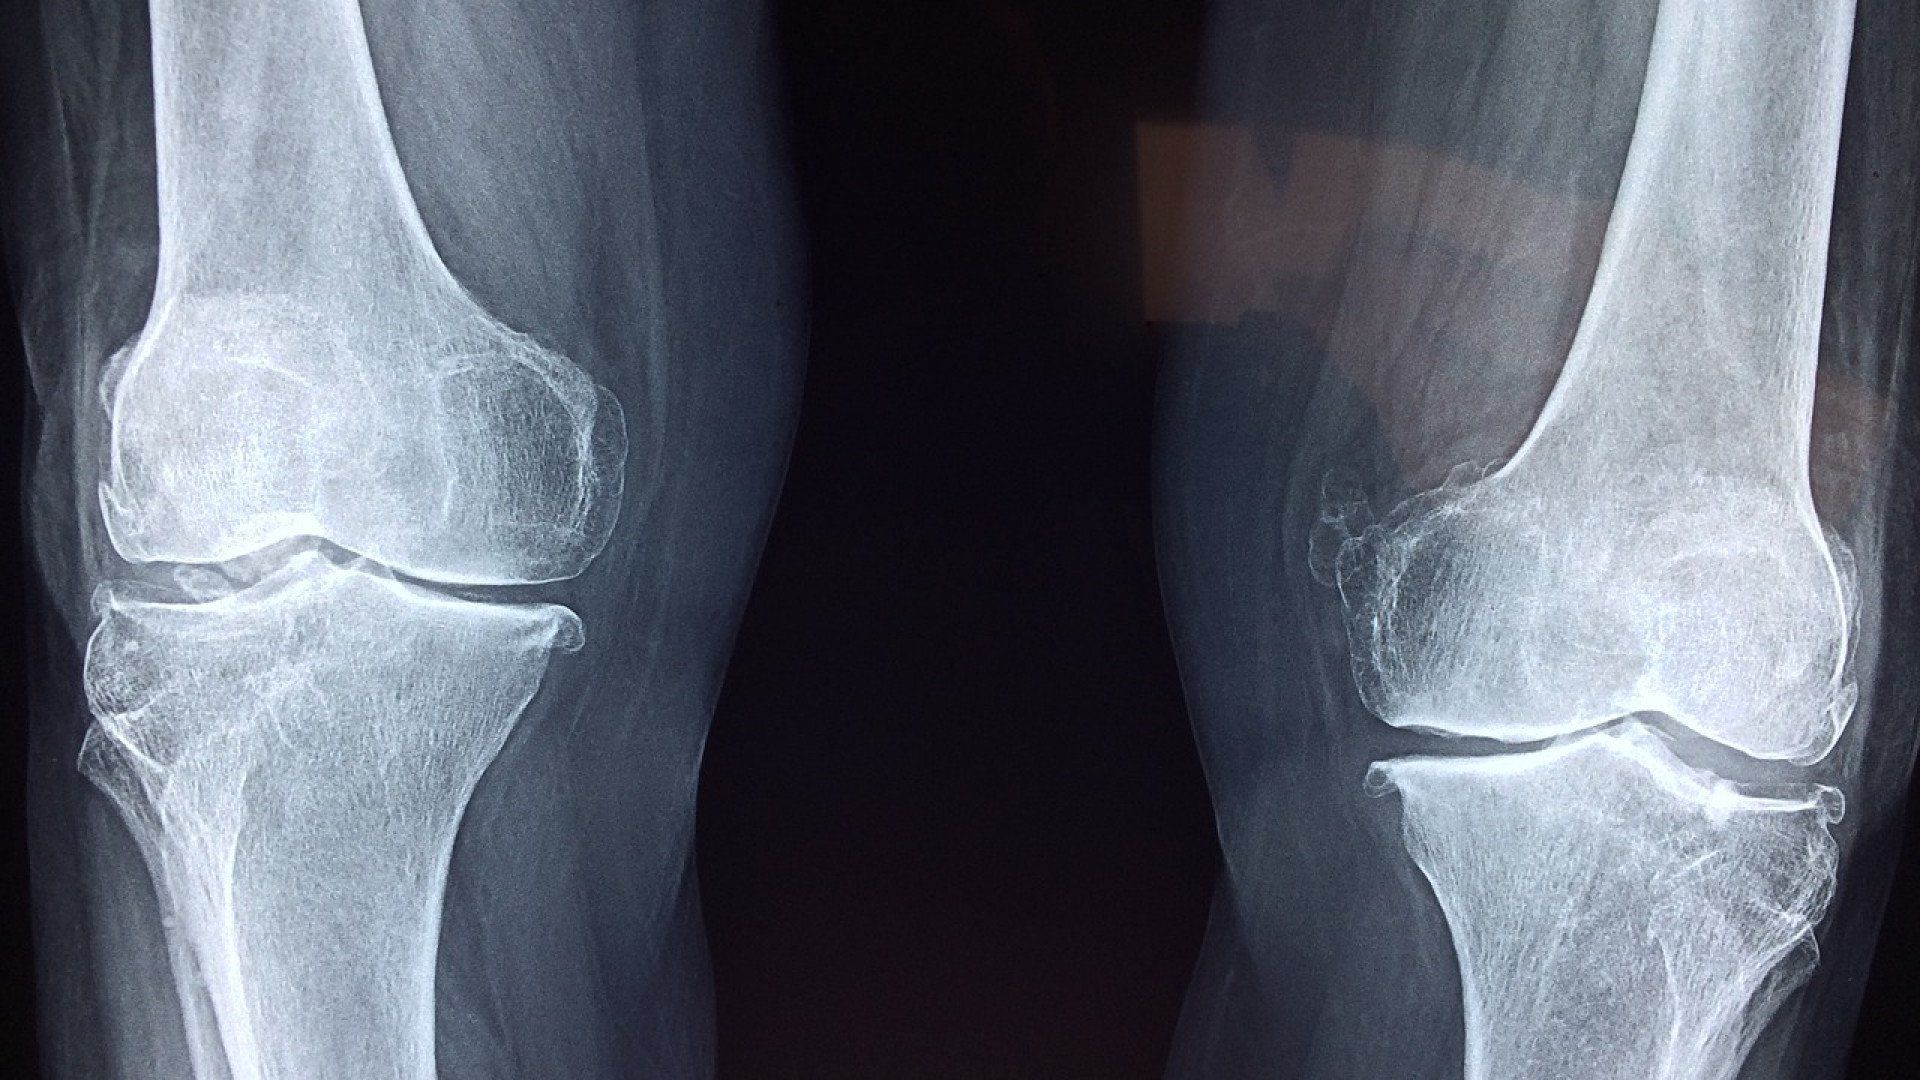

Le traitement et la prise en charge des “inhibitions motrices” devient un point de recherche central dans la rééducation fonctionnelle. On voit les études cliniques se multiplier sur le sujet depuis quelques années, notamment dans le cadre de leur apparition après chirurgie du LCA, où l’on parle plus précisément d’“arthrogenic muscle inhibition” (AMI). Dans ce cas précis, il s’agit d’une sidération persistante du quadriceps qui se caractérise par une incapacité à recruter correctement les fibres du muscle. Lors de l’apparition de ce type de phénomènes, on observe donc plusieurs conséquences directes, qui seront autant de freins à la rééducation fonctionnelle du membre touché, et aboutiront à des schémas compensatoires plus ou moins impactants, voire handicapants pour la motricité des patients.